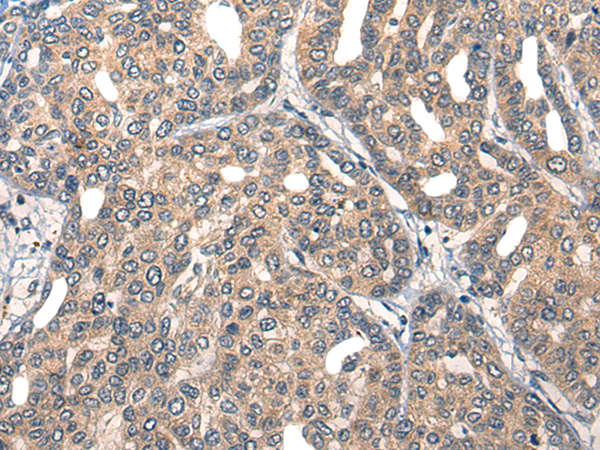

分类: 科研抗体货号: P13159别名: HNRPR; hnRNP-R应用: IHC反应种属: Human